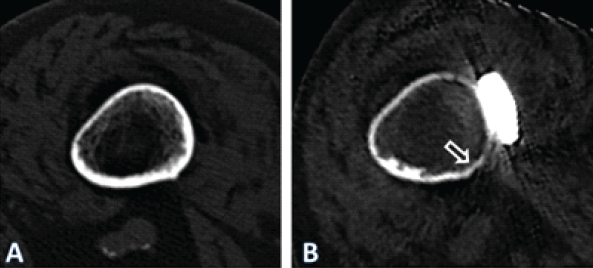

Figure 4: Axial computed tomography (CT)-scan images illustrating the cross-section of the femoral diaphysis of the patient described, at the level of the yellow line in Fig. 1. In (a) at the time of the periprosthetic fracture. In (b) 4 years after internal fixation with a lateral plate. Note general atrophy with thinning out of the cortex. In the area under the plate (ar-row), there were areas of necrosis, with no detectable bone metabolism in a single-photon emission CT. The quality of the image in (b) is reduced due to artifacts caused by the im-plants and due to the movement of the patient during the procedure. Only the geometry of the bone may be compared. The apparent density of the bone is affected by differing acqui-sition protocols as well as due to artifacts induced by the implants, limiting comparison of the density

As the treating team considered the stem to be stable, with a fracture evaluated as being located distally to the area of fixation (Unified Classification System [UCS] Type C) [17], plate fixation was chosen. Open reduction and internal fixation of the fracture was performed through a subvastus approach, with reduction and fixation by a cable cerclage (Cable System 1.7 mm, DePuy Synthes, Zuchwil, Switzerland) and application of a lateral neutralization plate (non-contact bridging [NCB] Periprosthetic Femur Plate System 18 hole, Zimmer Biomet, Zug, Switzerland), fixated distally with screws and along the level of the stem with further cable cerclages (Cable System 1.7 mm). Postoperatively, the patient was mobilized in a wheelchair, as full weight-bearing was not recommended and as it was not possible to implement partial weight-bearing. Wound healing was uneventful. The radiological follow-up after 8 weeks showed intact material without evidence of loosening (Fig. 1c). Mobilization under full weight-bearing with support by physical therapy was then attempted. Four months postoperatively, the radiological follow-up showed a general atrophy of the cortical bone, which was accentuated at the lateral cortex, underneath the plate (Fig. 1d). Mobilization was hampered due to thigh pain, which had been interpreted to be caused by muscle atrophy. Thus, further physical therapy was recommended. As the impaired mobility caused difficulties attending consultation at the hospital, no further follow-up visits were planned. Due to increasing thigh pain, the patient was readdressed for evaluation by her general practitioner 4 years after the operative treatment of the PPF. Not having been mobilized outside a wheelchair in the meantime, the patient showed bilateral hip and knee flexion contractures. Consequently, she was unable to stand, disregarding the issue of thigh pain. Radiologically, there was now pronounced atrophy of the cortical bone of the femur, particularly of the lateral cortex under the plate (Fig. 1e). An infection was considered unlikely, as there was no pain at rest, as the soft tissues were inconspicuous, as the fracture had healed, and as there were no general symptoms. A single-photon emission computed tomography (CT) showed avascular areas of cortical bone underneath the plate (Fig. 3). The CT better illustrated a general atrophy of the femur with thinning of the bone cortex in comparison to the contralateral femur (Fig. 4 and 5). There was, however, no sign of loosening of the stem. Considering comorbidities, very limited potential for recovery, and the patients’ desire for no more surgery, the option of a revision was rejected, accepting the present situation. The patient died 7 months later.